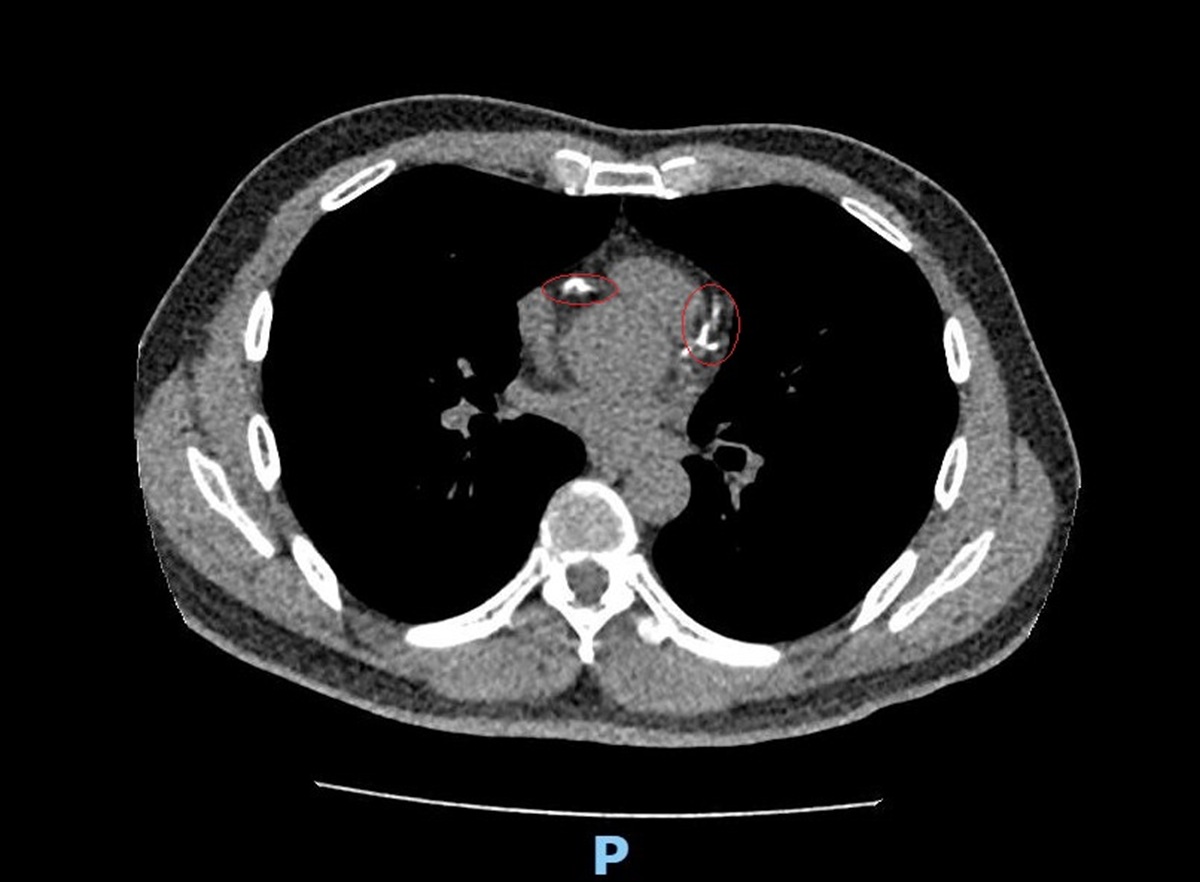

李學林表示,林先生日前接受肺癌篩檢時意外發現心血管鈣化,但無法確認是血管內或血管外鈣化。因患者平時已出現胸悶症狀,進一步做心臟冠狀動脈電腦斷層,確認為3條主要冠狀動脈血管內鈣化狹窄達85%以上,若未及時處理,隨時可能引發急性心肌梗塞。

李學林說,醫療團隊透過心導管手術搭配 IVL技術,利用震波氣球貼近血管壁發出超聲壓力波,擊碎血管壁的堅硬鈣化斑塊,讓原本僵硬的血管恢復擴張性,為支架放置創造理想的環境,再植入3支支架,使支架能完整展開、貼合血管,降低支架血栓及再狹窄的風險。